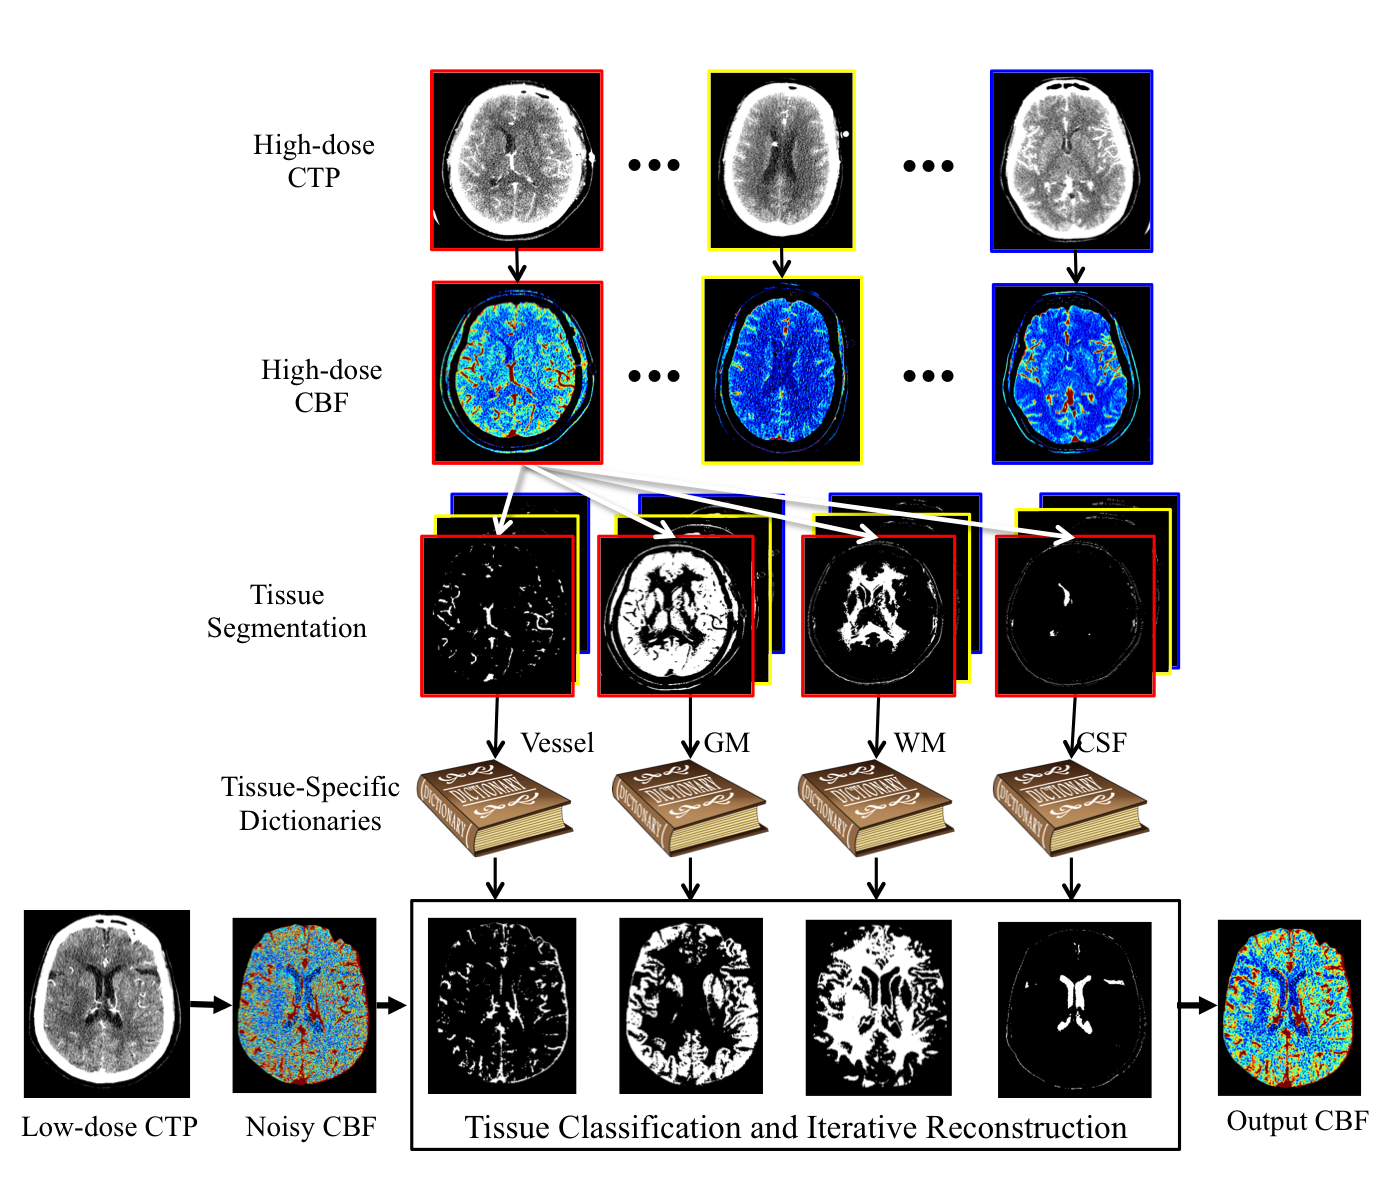

Sparse perfusion deconvolution has been recently proposed to effectively improve the image quality and diagnostic accuracy of low-dose perfusion CT by extracting the complementary information from the high-dose perfusion maps to restore the low-dose using a joint spatio-temporal model. However the low-contrast tissue classes where infarct core and ischemic penumbra usually occur in cerebral perfusion CT tend to be over-smoothed, leading to loss of essential biomarkers. In this paper, we extend this line of work by introducing tissue-specific sparse deconvolution to preserve the subtle perfusion information in the low-contrast tissue classes by learning tissue-specific dictionaries for each tissue class, and restore the low-dose perfusion maps by joining the tissue segments reconstructed from the corresponding dictionaries. Extensive validation on clinical datasets of patients with cerebrovascular disease demonstrates the superior performance of our proposed method with the advantage of better differentiation between abnormal and normal tissue in these patients.

Algorithm

- STEP 1:Tissue Classification. Classify the voxels in CTP into four classes: vessel, gray matter (GM), white matter (WM) and cerebrospinal fluid (CSF).

Use Expectation-Maximization Segmentation (EMS) with contexture information incorporated by a MRF.

- STEP 2: Tissue-Specific Dictionaries Learning. Use online dictionary learning. Patches with 50% or more pixels in class i are used for training dictionary Di.

- STEP 3: Weighted Sparse Deconvolution. Reconstruct the CBF map for each tissue class using the respective dictionary.

Weighted sum for each pixel based on the classification probability map.